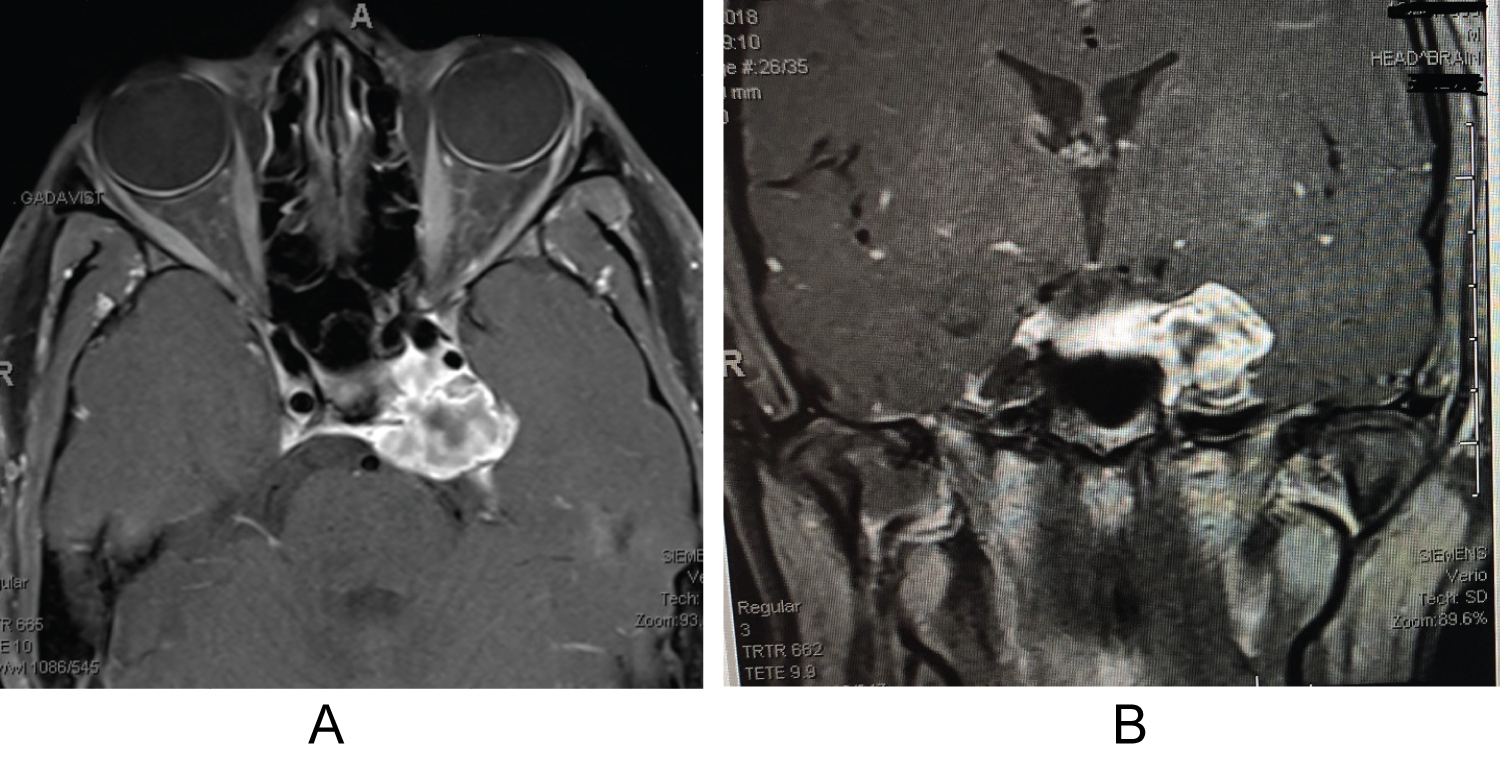

An 18-year-old male with no significant past medical history presented with a three week history of worsening left monocular diplopia and compensatory head tilt. Five months prior to presentation left sided neglect was noted by his father. He denied any associated symptoms including headaches, nausea, fatigue, bone/back/neck pain, or changes in cognition/speech/hearing. Initial neurological examination revealed left abducens nerve palsy and partial left trochlear nerve palsy, as well as anisocoria with left pupil larger than the right. The patient underwent brain and orbital magnetic resonance imaging (MRI) revealing a 27.3 × 29.0 × 18.6 mm left cavernous sinus mass arising from the petrous apex with extension into the cavernous sinus and the Dorello's canal; such findings are consistent with the presenting symptoms (Figure 1A and Figure 1B). The CT scan confirmed a calcified mass (Figure 2A and Figure 2B). Patient was hospitalized and scheduled for resection of the left cavernous sinus.

Figure 2: (A,B) Pre-operative axial and coronal brain CT with contrast shows the partially calcified mass arising from the left cavernous sinus with mass effect on mesial temporal lobe. View Figure 2

During the three month follow up visit, there was residual diplopia and decreased sensation upper part of left forehead (V1 distribution). At the 12-month follow up visit, the patient reported persistent but much improved CN VI palsy with intermittent conjunctival irritation and persistent decreased sensation at left cranial nerve V1 distribution. 12-month post-op MRI noted improved decompression of the cavernous sinus and residual postoperative enhancement along left petroclinoid ligament with extension toward the cavernous sinus (Figure 3A and Figure 3B).

Figure 3: (A,B) 12 months post-operative axial and coronal brain MRI imaging using T1 sequence with contrast shows gross total resection of the cavernous sinus mass with improved mass effect on mesial temporal lobe and ICA artery. View Figure 3